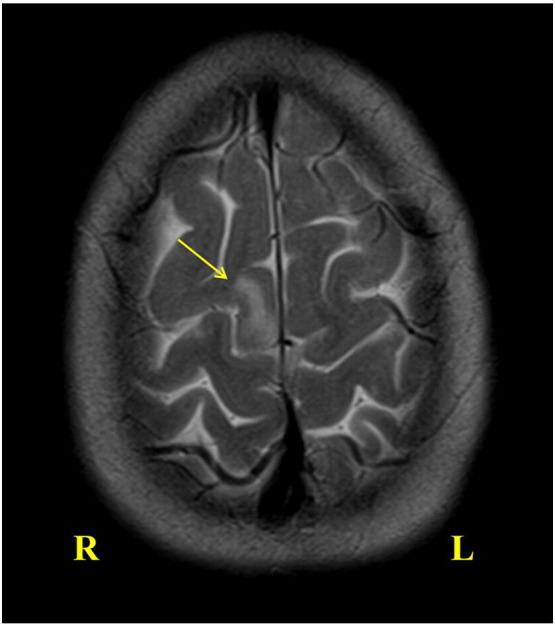

A 7-year-old previously healthy girl presented with a left-sided focal seizure without impaired consciousness and subsequently developed epilepsia partialis continua. Initial MRI was normal, and the subsequent images only showed a focal T2/FLAIR hyperintense area without cortical atrophy. She was diagnosed with Rasmussen syndrome by pathology and promptly treated with functional hemispherotomy. Rasmussen syndrome is a rare progressive neurological disorder, the only definitive cure for which is hemispheric disconnection. The disease presents a management dilemma, especially early in disease course without characteristic neuroimaging features. A high index of suspicion, multidisciplinary approach, and clear timely communication with the family are critical.

一名7岁的既往健康女孩出现左侧局灶性癫痫发作,意识未受损,随后发展为持续性部分性癫痫。初次MRI检查正常,后续影像仅显示一个局灶性T2/FLAIR高信号区,无皮质萎缩。经病理诊断为拉斯穆森综合征,并立即接受了功能性大脑半球切除术治疗。拉斯穆森综合征是一种罕见的进行性神经疾病,唯一的确切治疗方法是大脑半球离断术。该疾病带来了治疗难题,尤其是在病程早期没有特征性神经影像学表现时。高度的怀疑指数、多学科方法以及与家属清晰及时的沟通至关重要。